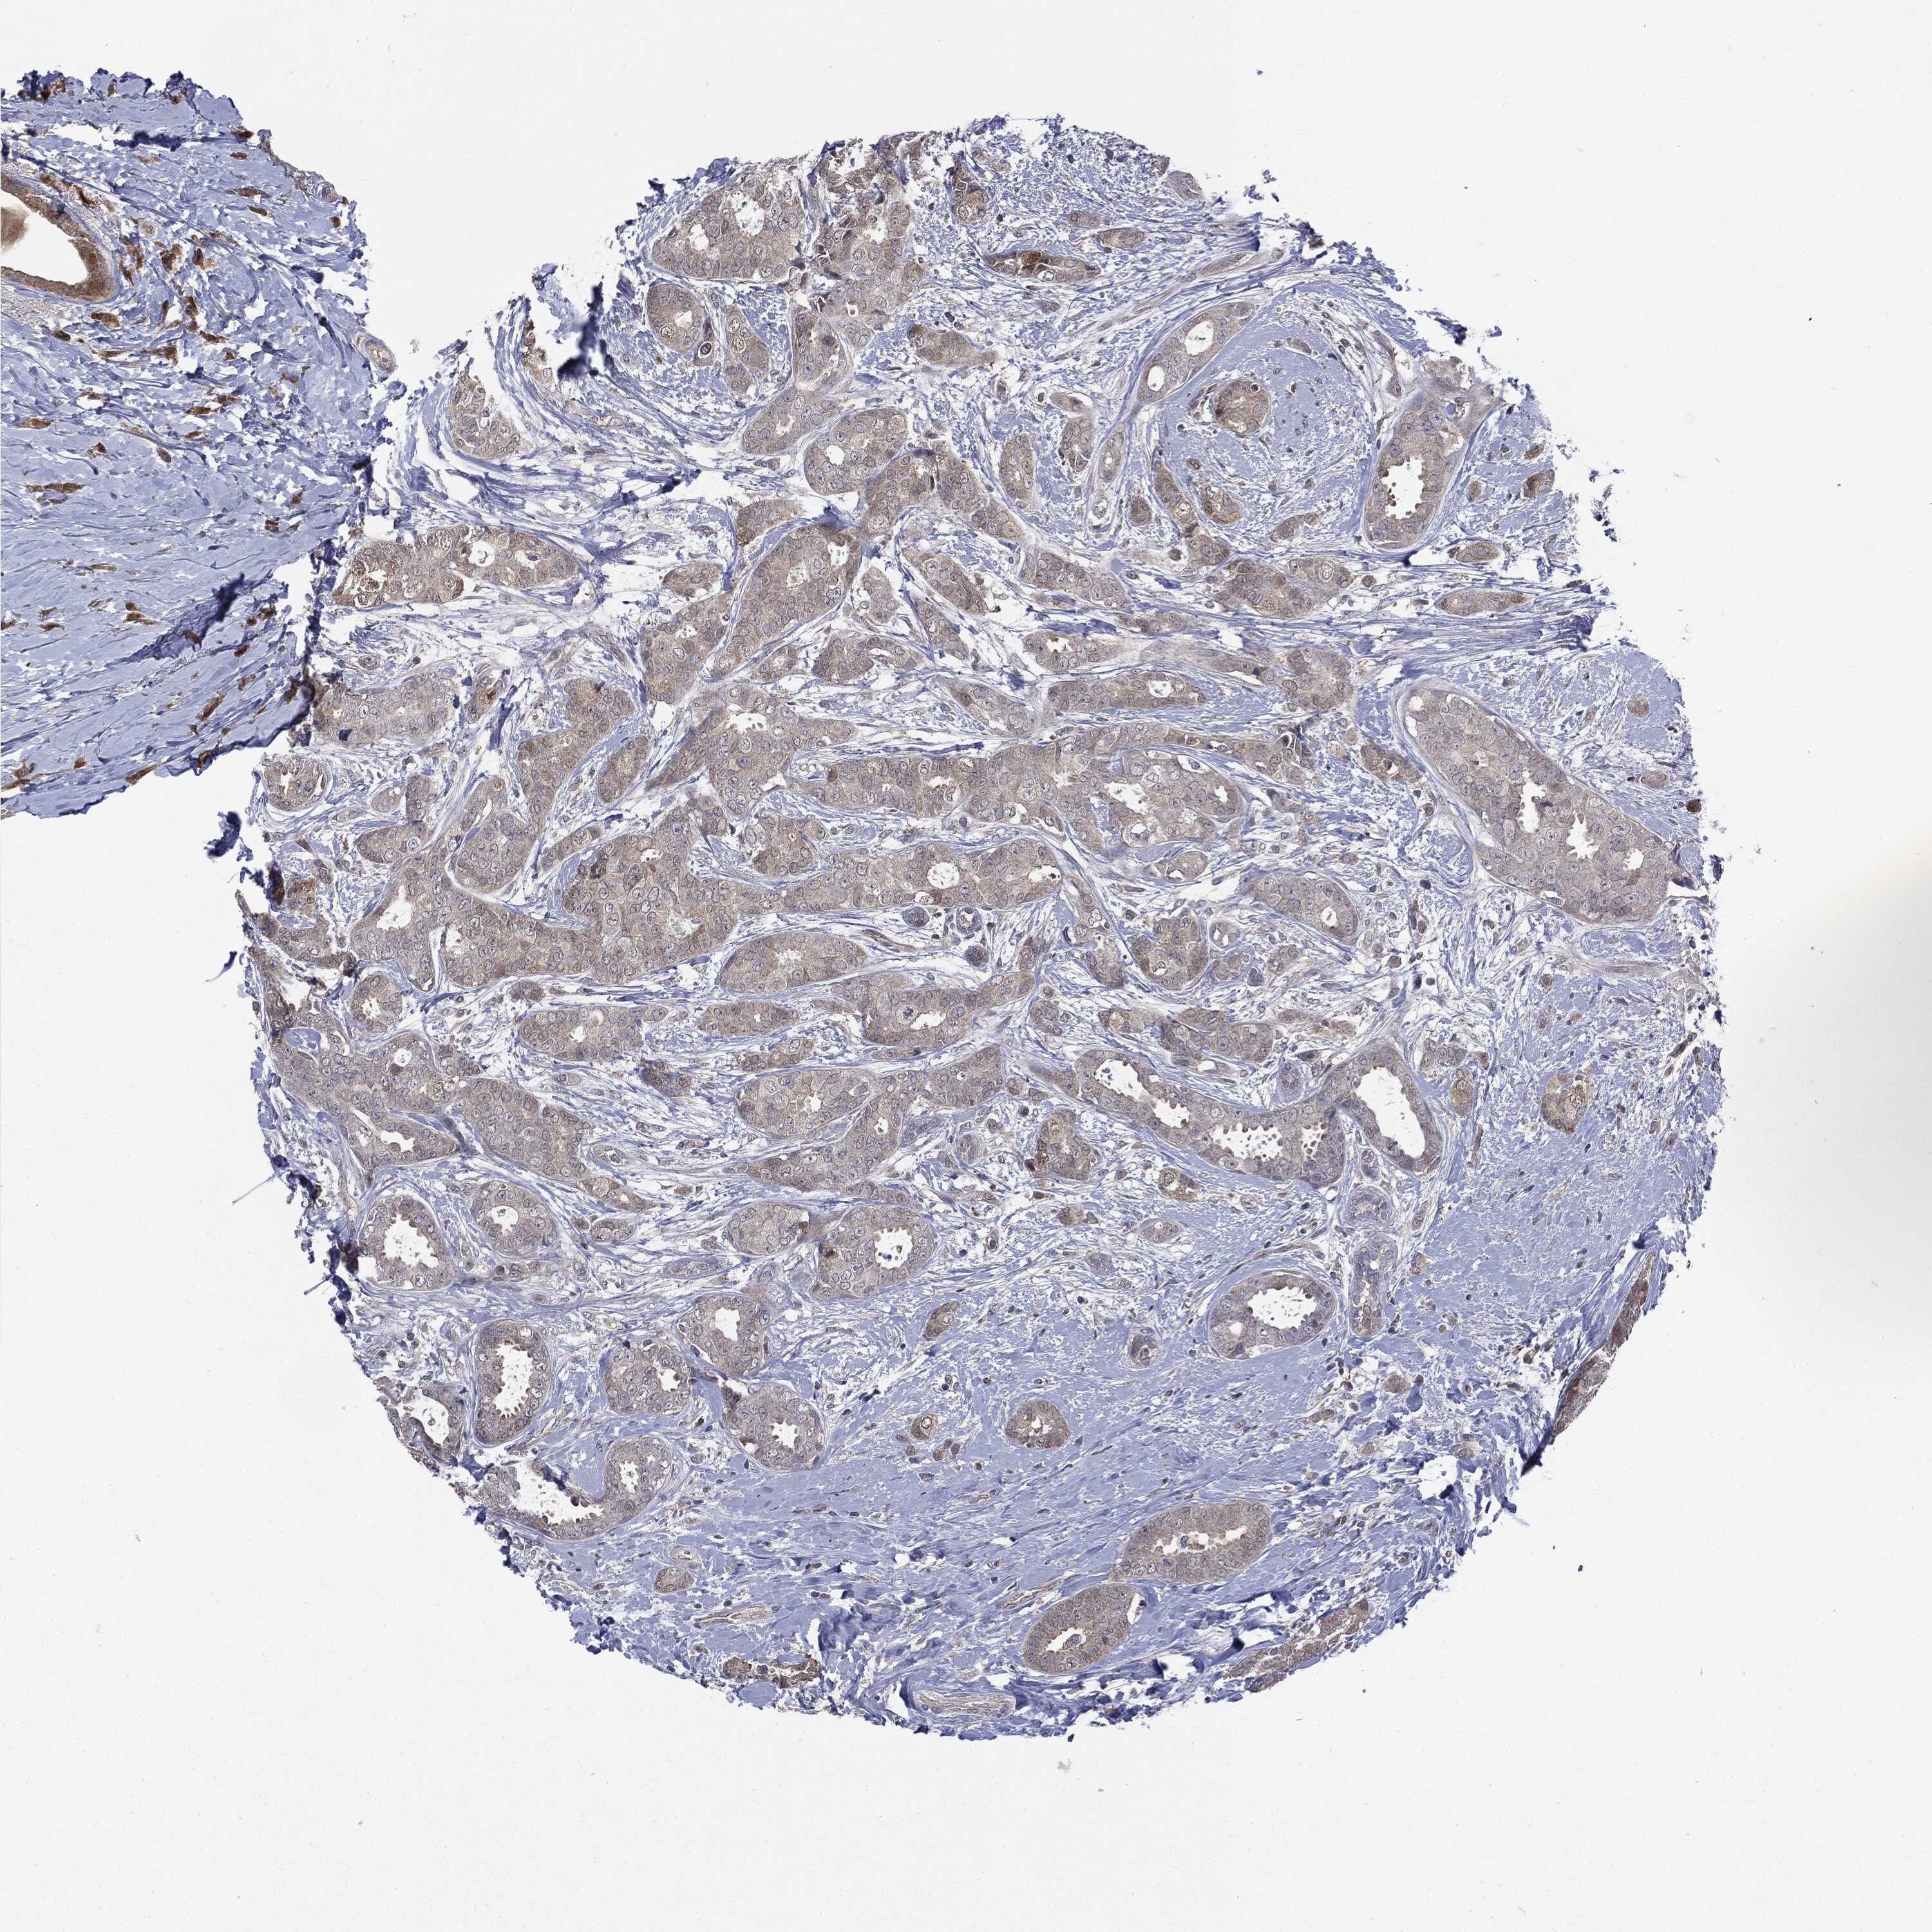

CANCER BREAST CANCER Show tissue menu

BRCA TCGA BRCA VALIDATION PROTEIN EXPRESSION

ANTIBODIES

AND

VALIDATION